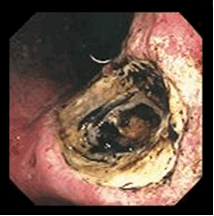

Рис.2. Пенетрация язвы желудка

Рис.3. Малигнизация язвы желудка